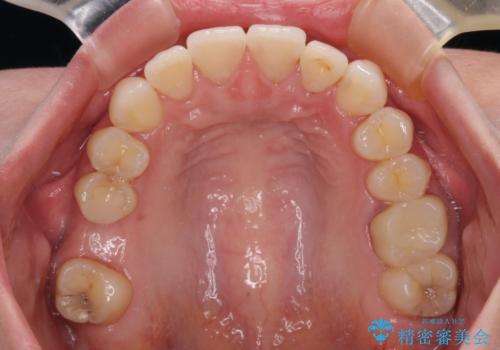

矯正治療後半に奥歯の補綴治療が必要な歯にはオールセラミッククラウンを装着し、インビザラインで最終的に仕上げることとしました。

海外に行く前に口腔内環境を整えることができ、患者様には大変満足していただきました。